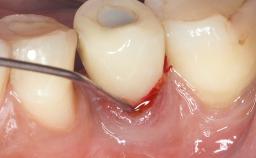

Treatment of Advanced Peri-Implantitis by Implant Removal Followed by Bone Reconstruction and New Implant Placement

Paolo Casentini and Matteo Chiapasco present a case in which the peri-implant defect was not suitable for a fully regenerative approach. It involves implant removal, use of a CAD/CAM customized titanium mesh in the grafting phase, and placement of new implants. A 62-year-old woman was referred for consultation regarding her implant-supported prosthesis replacing teeth 14 to 16. The patient’s main concern was pain and recurrent swelling in the right posterior maxilla. The patient also reported difficulty and discomfort when brushing the area. The patient reported she had been treated in another country, where she had received three implants in combination with sinus-floor augmentation for the replacement of the posterior maxillary teeth three years earlier. The patient indicated “endodontic complications” to be the reason for the extraction of the teeth.